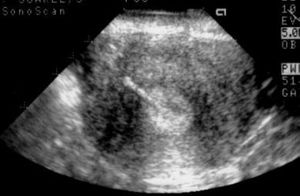

Implantation in the scar of a previous Cesarean is thought to be the rarest of ectopic pregnancies. With the increasing numbers of Cesareans performed, scar implantation may become more frequent as well. We present an illustrative case.